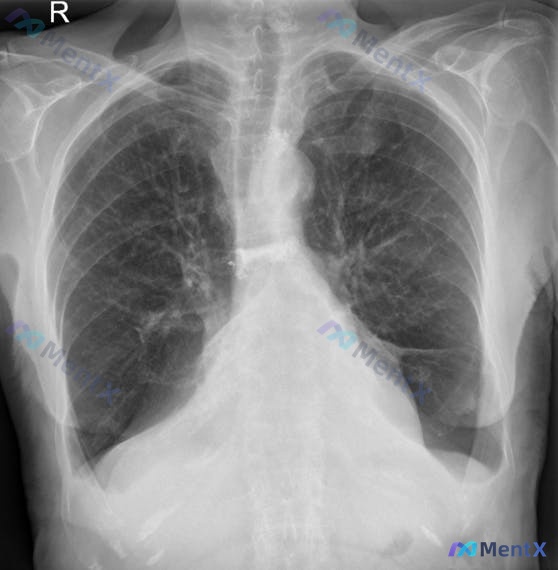

整理了一个有点“陷阱”的术后病例,先抛出来大家一起理理思路。 基本情况:47岁男性,因持续胆绞痛20年前接受择期腹腔镜胆囊切除术(无手术并发症报告),另有持续性高脂血症,目前有吸烟史(原文表述为“药物烟”,暂按吸烟史处理)。 本次情况:术后持续出现新发发热。 查体:T 101.2 ºF(约38.4℃...